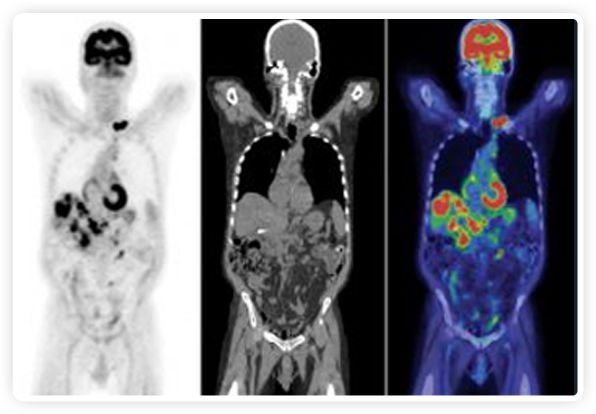

提起放療設備的引導系統(tǒng),大家通常會想到結(jié)構性成像的CT或核磁。但你有沒有想過用功能性成像來引導放療呢?美國的一家醫(yī)療器械公司從2011年就致力于研究開發(fā)用PET提供生物學指導放射治療的設備BgRT。BgRT能實時利用癌癥的生物學特征作為信號指導治療全身腫瘤。

正電子發(fā)射斷層掃描(PET)是癌癥檢測中已建立的成像標準,與其他成像方式相比,PET能提供高靈敏度和特異性的圖像。

到目前為止,放射腫瘤學中(使用的圖像主要是結(jié)構性的,而PET圖像可以提供生物學信息。通過使用注射示蹤劑,例如18-FDG,PET可以描繪腫瘤的代謝活性,使其“點亮”。(FDG是用于可視化癌癥代謝的最廣泛使用的示蹤劑。與正常組織相比,腫瘤細胞保留更高水平的FDG。)不同的PET示蹤劑可以識別腫瘤的不同生物學特征,例如特定生物標志物抗原(例如,PSMA)或甚至探測免疫系統(tǒng)本身(例如,PDL1表達或活化的T細胞)。

PET+放療共同治療

RefleXion將PET成像與立體定向放射治療相結(jié)合。在注射示蹤劑后,RefleXion的技術基于示蹤劑信號實時地在一個或多個目標上引導治療性X射線。使用這種專有方法,RefleXion的平臺有可能比現(xiàn)有系統(tǒng)向癌癥病變提供更高劑量的輻射,并改善周圍健康組織的保護。